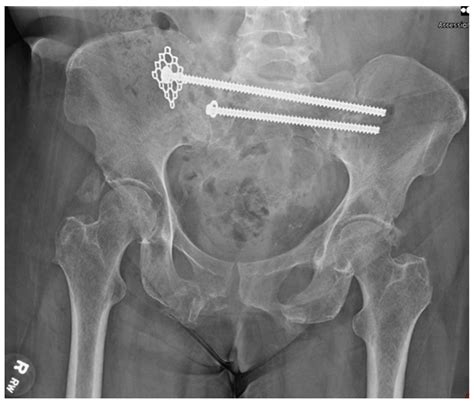

Another important clinical consideration is the role of the sacral alae in spinal surgeries. During procedures such as spinal fusion or sacroiliac joint fusion, the sacral alae serve as critical landmarks and attachment points for surgical hardware. Proper understanding and visualization of these structures are essential for successful surgical outcomes.

• X-rays: Provide a basic overview of the bone structure and can help identify fractures or dislocations.

• Fractures: Fractures of the sacral alae can occur due to trauma or osteoporosis. These fractures can be painful and may require surgical intervention.

• Surgery: In severe cases, surgical intervention may be required to repair fractures, stabilize joints, or remove tumors.